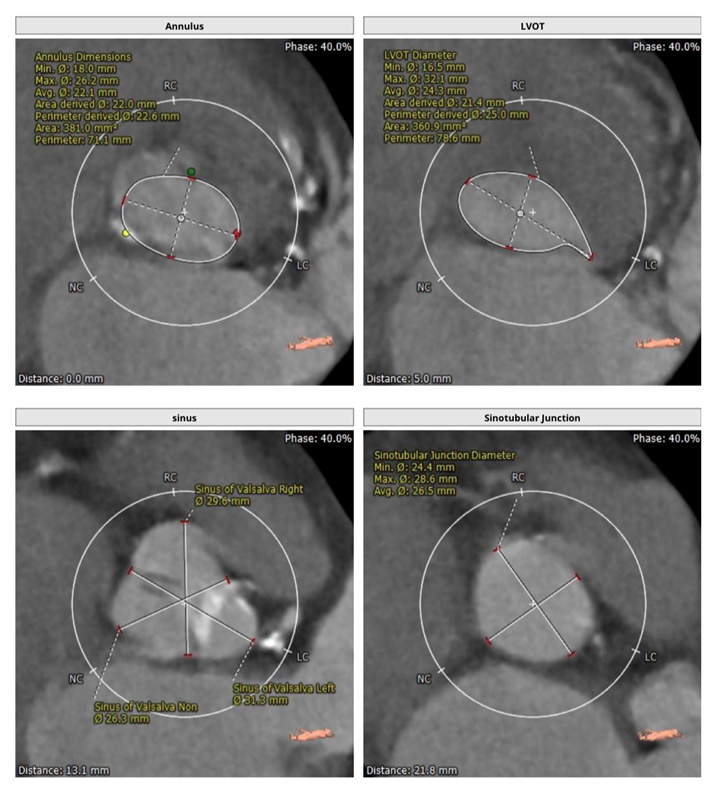

主动脉根部解剖CT影像

瓣环平均直径:22.1 mm,左室流出道平均直径:23.7mm。

升主动脉(未见)明显扩张,心脏角度:48°。

左冠高度:9.6 mm,右冠高度:16.1 mm。

钙化积分:157mm³,轻度钙化。

钙化积分:221.4mm³。